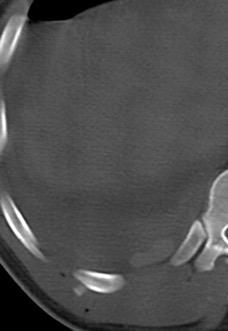

Empiema pleural en adicto. “Borde bien definido”.

DD et al . Differentiating abscess and empiema: Radiography and computed tomography. AJR.1983